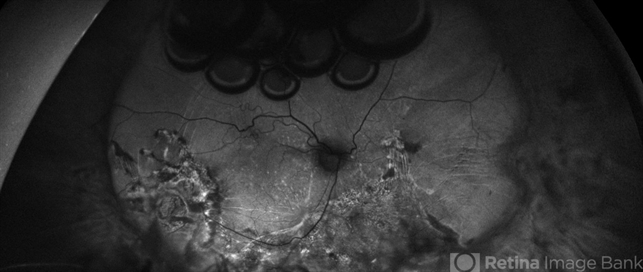

- Pseudophakic RRD status post Buckle Vitrectomy with Residual Gas Fish Eggs OD

- encircling scleral buckle, intraocular gas, gas bubble, intravitreal gas bubble

- 71-year-old male, s/p combined buckle vitrectomy for recurrent, macula-off, rhegmatogenous retinal detachment, with residual gas fish eggs OD.